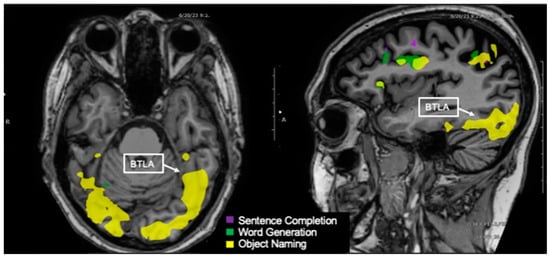

3.11. Basal Temporal Language Area